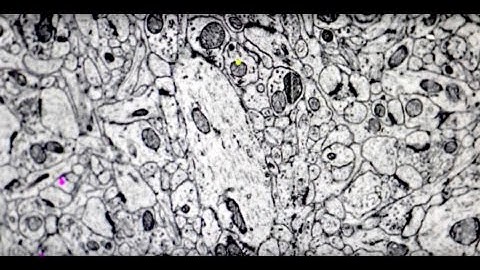

Powers of Ten in Big Data Connectomics